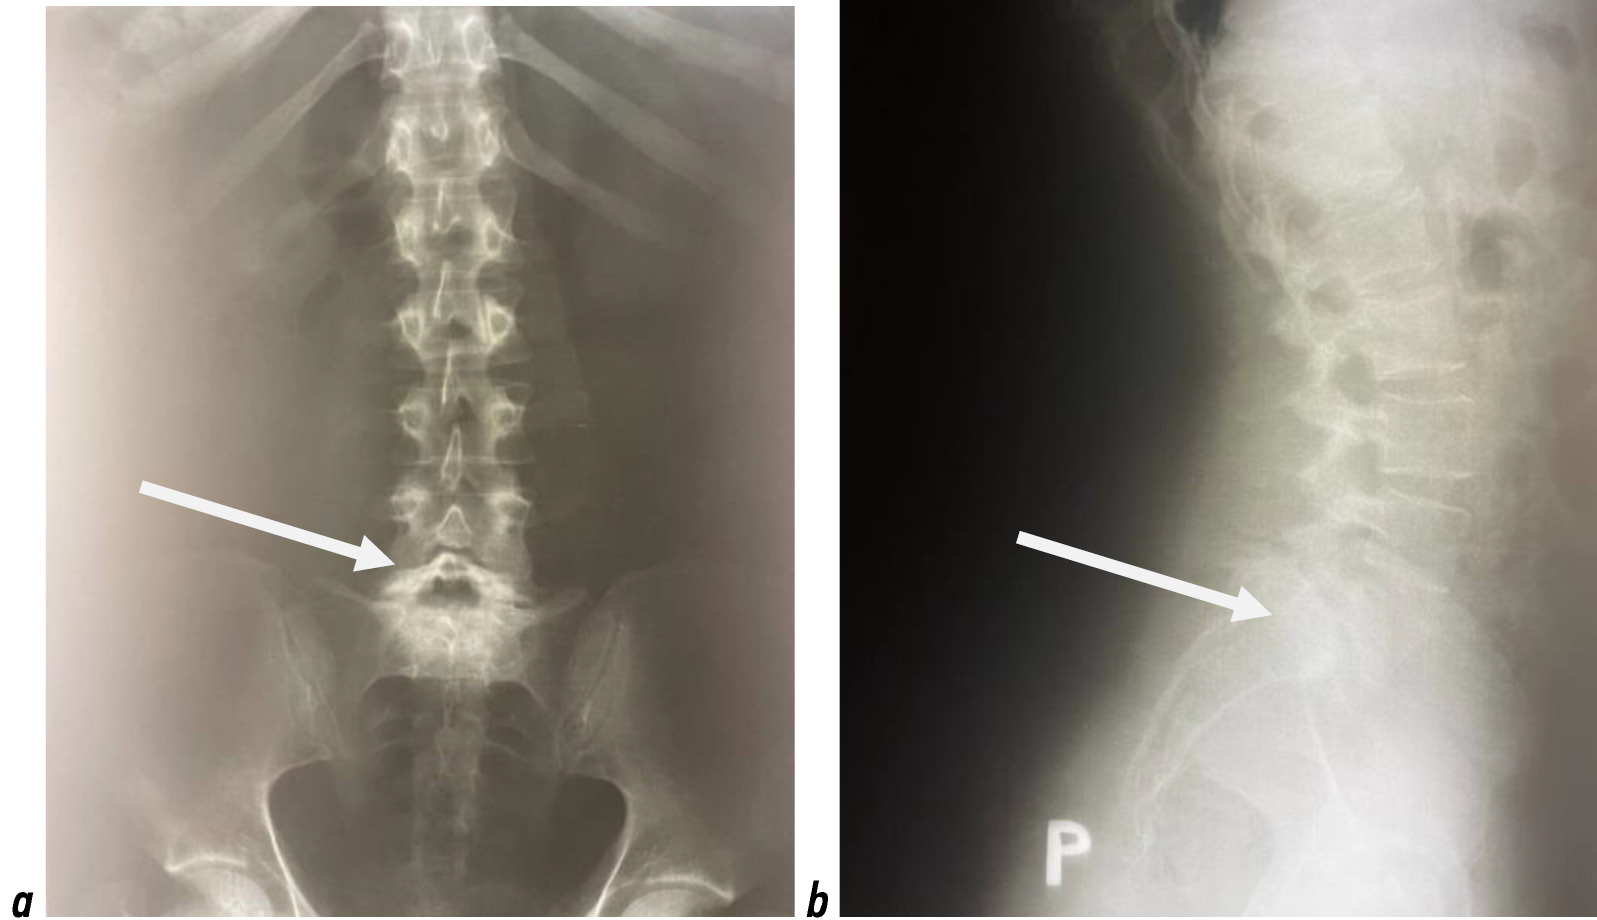

Учитывая клинико-рентгенологическую картину, пациентке было выполнено хирургическое лечение: дорсальная стабилизация позвоночника ригидной системой, ламинэктомия на уровне L5–S1, декомпрессия позвоночного канала, межтеловой корподез на уровне L5–S1 кейджем, задний спондилодез ауто- и аллокостью. Эффект от оперативного вмешательства был достигнут ― болевой синдром регрессировал полностью. По данным контрольной рентгенографии позвоночника в 2018 году, состояние металлоконструкции корректное (рис. 2).

Рис. 2. Рентгенограмма пояснично-крестцового отдела позвоночника пациентки Ф. после операции: а ― фронтальная проекция; b ― сагиттальная проекция

Fig. 2. X-ray of the lumbosacral spine of patient F. after operation: а ― frontalis projection; b ― sagittalis projection.